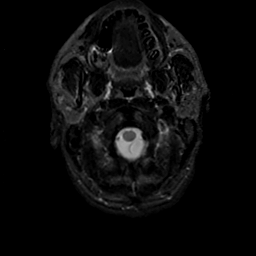

MR Study #18, July 21, 1991 -- Slice #1

[Home][Help][Clinical][Tour 1][Tour 2] Slice 1